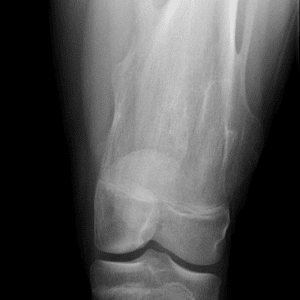

Pediatric Radiographs